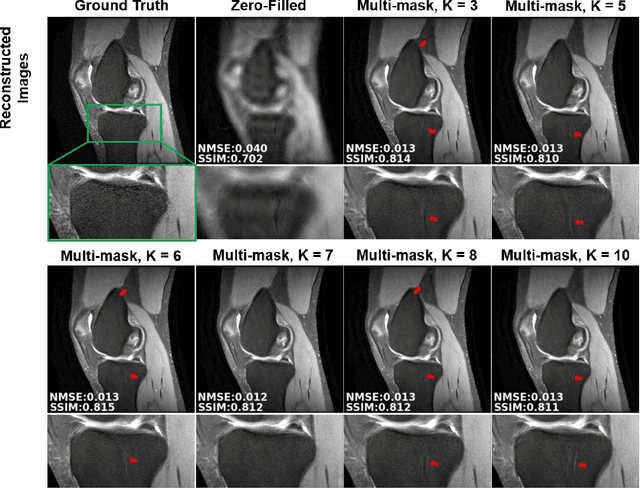

Abstract:Physics-guided deep learning (PG-DL) via algorithm unrolling has received significant interest for improved image reconstruction, including MRI applications. These methods unroll an iterative optimization algorithm into a series of regularizer and data consistency units. The unrolled networks are typically trained end-to-end using a supervised approach. Current supervised PG-DL approaches use all of the available sub-sampled measurements in their data consistency units. Thus, the network learns to fit the rest of the measurements. In this study, we propose to improve the performance and robustness of supervised training by utilizing randomness by retrospectively selecting only a subset of all the available measurements for data consistency units. The process is repeated multiple times using different random masks during training for further enhancement. Results on knee MRI show that the proposed multi-mask supervised PG-DL enhances reconstruction performance compared to conventional supervised PG-DL approaches.

Abstract:Purpose: To develop an improved self-supervised learning strategy that efficiently uses the acquired data for training a physics-guided reconstruction network without a database of fully-sampled data. Methods: Currently self-supervised learning for physics-guided reconstruction networks splits acquired undersampled data into two disjoint sets, where one is used for data consistency (DC) in the unrolled network and the other to define the training loss. The proposed multi-mask self-supervised learning via data undersampling (SSDU) splits acquired measurements into multiple pairs of disjoint sets for each training sample, while using one of these sets for DC units and the other for defining loss, thereby more efficiently using the undersampled data. Multi-mask SSDU is applied on fully-sampled 3D knee and prospectively undersampled 3D brain MRI datasets, which are retrospectively subsampled to acceleration rate (R)=8, and compared to CG-SENSE and single-mask SSDU DL-MRI, as well as supervised DL-MRI when fully-sampled data is available. Results: Results on knee MRI show that the proposed multi-mask SSDU outperforms SSDU and performs closely with supervised DL-MRI, while significantly outperforming CG-SENSE. A clinical reader study further ranks the multi-mask SSDU higher than supervised DL-MRI in terms of SNR and aliasing artifacts. Results on brain MRI show that multi-mask SSDU achieves better reconstruction quality compared to SSDU and CG-SENSE. Reader study demonstrates that multi-mask SSDU at R=8 significantly improves reconstruction compared to single-mask SSDU at R=8, as well as CG-SENSE at R=2. Conclusion: The proposed multi-mask SSDU approach enables improved training of physics-guided neural networks without fully-sampled data, by enabling efficient use of the undersampled data with multiple masks.